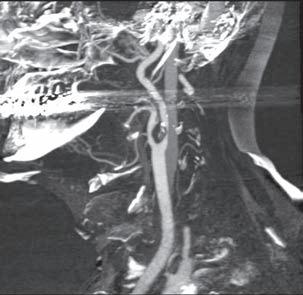

CT-angiografie tepen aortálního oblouku a intrakraniálních tepen i pro tuto oblast při diagnostice plně nahradila klasickou angiografii. DSA tak zůstává jako metoda pouze pro ověření nejasných nálezů nebo jako součást intervenčního výkonu. Problémy při interpretaci nálezu nastávají u artefaktů způsobených

zubní výplní nebo náplní koncentrované kontrastní látky v žilách horní končetiny po aplikaci. Typickým výskytem zúžení nebo uzávěrů jsou odstupy tepen z oblouku a odstupy vnitřní a vnější karotické tepny (obr. 1.8). Neobejdeme se při posouzení významnosti zúžení bez MIP a MPR rekonstrukcí v tenkých vrstvách vzhledem ke kalcifikacím ve stěně. Při tomto způsobu rovněž lépe hodnotíme ulcerace a nástěnnou trombózu. Karotický sifon je hůře přehledný pro kostěné struktury v okolí. Intrakraniálně jsou již tepenná a žilní fáze společně. Dobře přehledný je Willisův okruh i drobné periferní tepny. Kvalitně se zobrazují variace tepen, aneuryzmata a nádory.